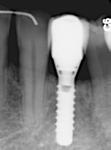

Patienttilfælde 1 (Fig. 1) er en 37-årig kvinde, henvist efter succesfuld behandling af stadie 3-parodontitis. Der er nu sundt

Før behandling

parodontium, ingen pocher over 4 mm, og både blødnings- og plakindeks er under 10 %. Patienten er motiveret for ortodontisk behandling, da hendes tænder er vandret over tid, delvist som følge af reduceret parodontium.

Der ses anterior trangstilling i begge kæber og overerupterede 1+1 og 2,1-1,2, hvilket resulterer i dybt bid med 2- tæt på ganepåbidning. Der er normale sidetandsrelationer, men der ses 5 mm horisontalt overbid (HOB) og 7 mm vertikalt

overbid (VOB). Papillen mellem 1+1 er betydeligt reduceret pga. fæstetab, og de mesialt kippede 1+1 har resulteret i en ”dark triangle”. Den facioorale funktion er for nuværende i.a. Panoramarøntgen (Fig. 1, I) viser marginalt knogletab i begge kæber og fravær af 8,7+7,8 og 8,7-8.